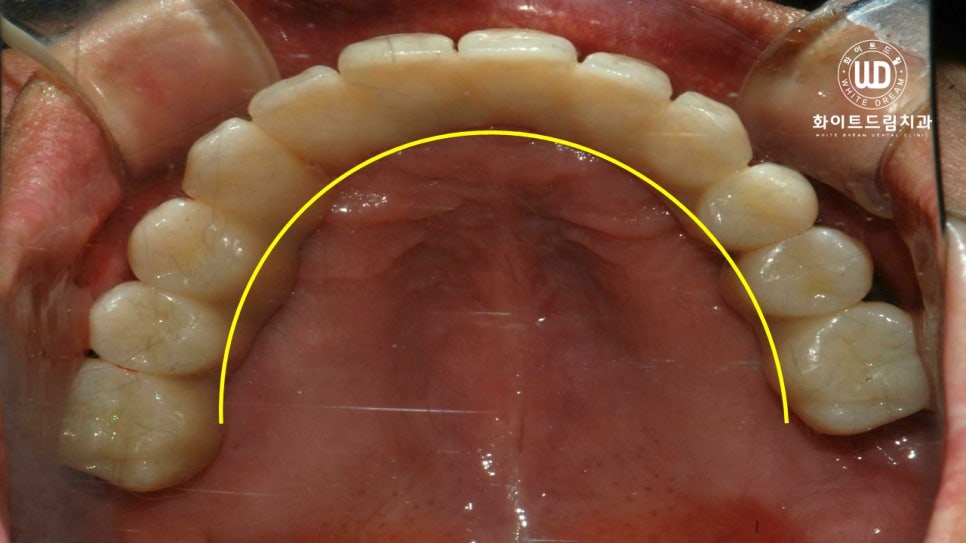

치료가 완료된 사진을 살펴보면 임플란트가 뿌리부터 머리까지 나란히 매끄럽게 연결되어 있는 것을 확인하실 수 있는데, 상악 하악의 U자 형태가 본 케이스와 같이 나올 수 있으려면 임플란트 보철 식립 방향을 잘 체크해야합니다.